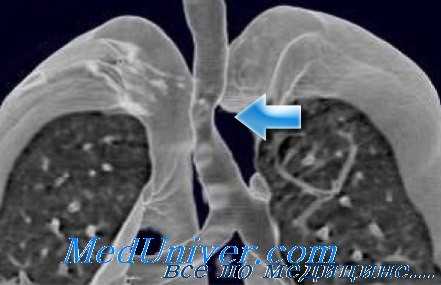

- верхней лоб(билоб)эктомии и резекции карины трахеи при перибронхиально-узловатом росте рака верхнедолевого бронха с переходом на боковую стенку главного до его проксимальной части и/или трахеобронхиального угла (рис. 2 );

- изолированной резекции бифуркации при опухолях с эндобронхиальным ростом в устье главных бронхов или дистального отдела трахеи. Подобные вмешательства выполнены 17 пациентам. Все они выписаны из стационара без осложнений. Лишь в 1 случае сформировался рубцовый стеноз в области устья промежуточного бронха, потребовавший эндоскопической реканализации бронха через 6 мес после оперативного вмешательства.